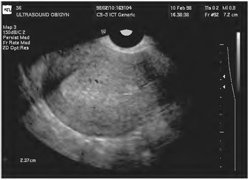

Hüvelyi méh hosszanti szkennelési egy beteg endometriális rák. Vastagság M-echo 23 mm

A hüvelyen át ultrahangos kép hosszanti letapogatott a méh. Vastagság M-echo nagy endometrium polipok (nyilak) eléri a 22 mm-es

A hüvelyen át ultrahangos kép hosszanti letapogatott a méh. Vastagság M-echo a méhnyálkahártya-hiperplázia (nyíl) a posztmenopauzális eléri 16 mm